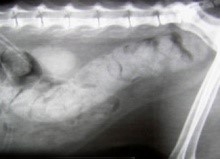

- опухоли кишечника или ануса, простаты у котов;

- увеличение толстого кишечника в объеме (мегаколон);

- проглоченные предметы, которые могут привести к разрыву кишечника и, в самых тяжелых случаях, к перитониту;